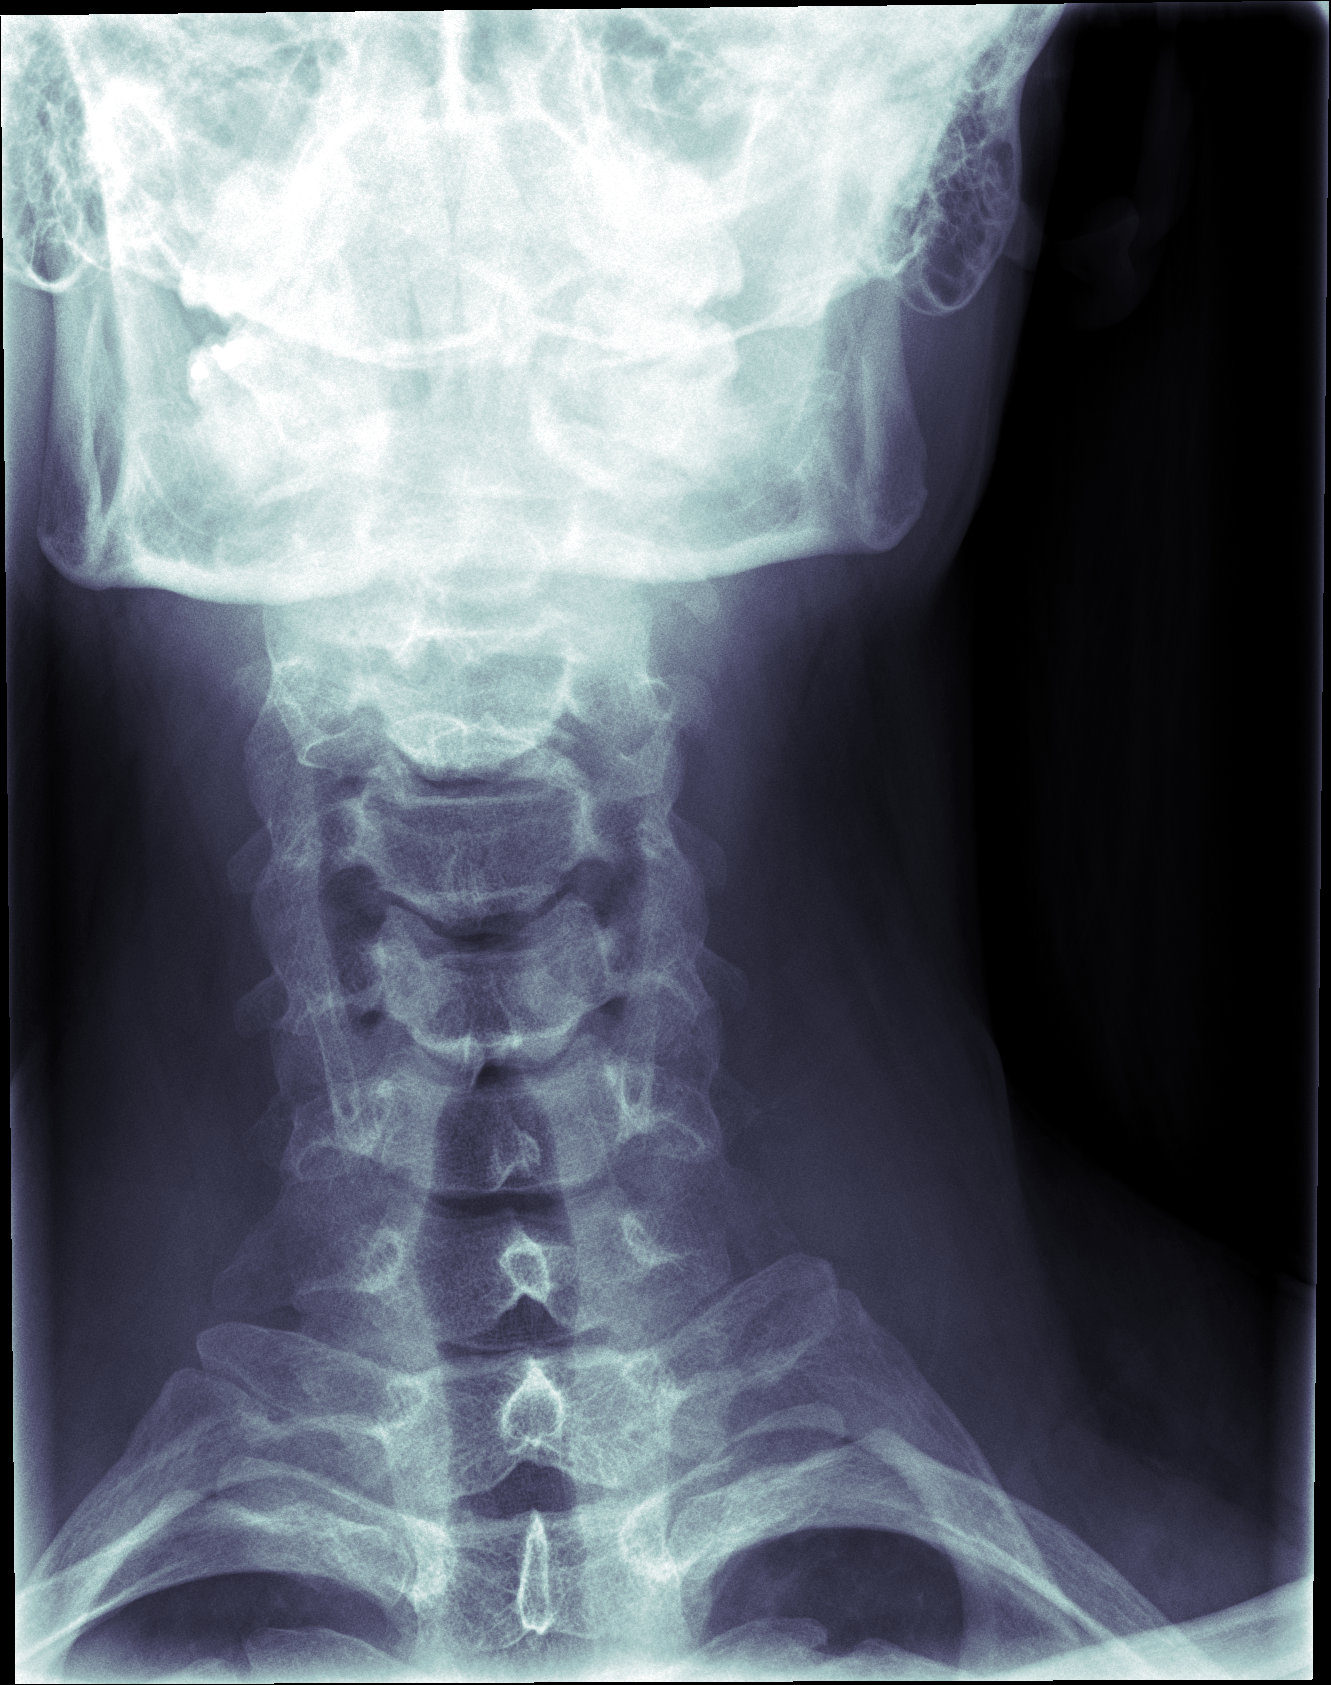

I like how my skull glows in this one, and how the vertebrae look when my neck is extended like that.